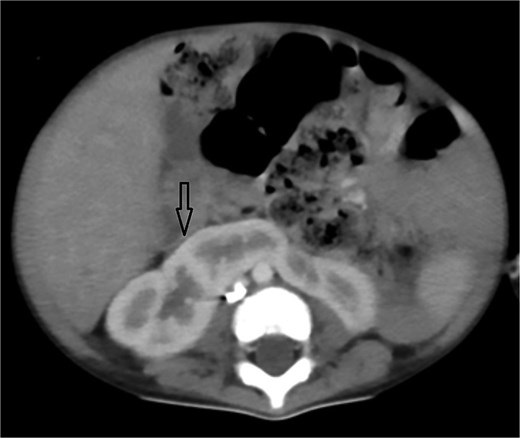

Axial abdominal CT showing central liver and polysplenism, compatible with left isomerism.

Urgent transthoracic echocardiography demonstrated a large echodense mass in the right hemithorax, compression of the right atrium and reduced flow through the right-sided shunt. Computed tomography angiography (CTA) confirmed a massive saccular pseudoaneurysm (≈8 × 7 × 6 cm) arising from the anastomosis between the right subclavian artery and the mBTTS graft, completely thrombosed without active contrast extravasation (Fig. 1). There was complete thrombotic occlusion of the right pulmonary artery, right lung collapse due to extrinsic compression and right lower-lobe consolidation consistent with pneumonia (Fig. 2). CTA also revealed left isomerism with central liver and polysplenism (Fig. 3) and a horseshoe kidney (Fig. 4), suggesting a previously unrecognized polymalformative syndrome.